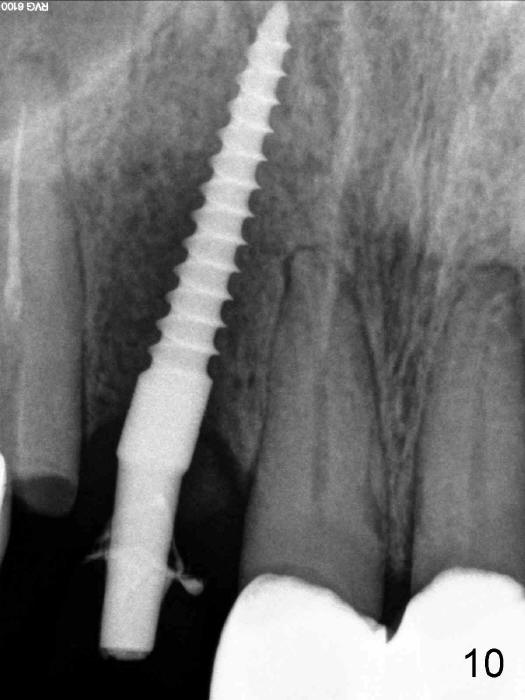

Finally the displaced implant is exfoliated itself, leaving a crater (Fig.1 arrowheads). CBCT shows the knife-edged ridge post exfoliation of the implant at the site of #7 (Fig.5, as compared to that prior to exfoliation). After using 1.5 mm pilot drill at 17 mm and 2.0 mm at 14 mm (Fig.5 insert), a 3.0x17 mm one piece angled (15 º) implant is placed (Fig.2, 10). Palatal view reveals that the implant is placed buccally (Fig.3); ideally the implant should be more palatal (Fig.3 insert: circle). Please take postop CBCT to confirm the placement. The buccal placement is partially related to the elongated tooth (Fig.4).